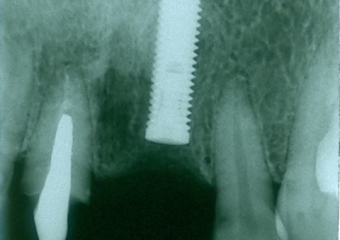

Imagens do caso inicial, com presença de fratura radicular do dente 21

Raio X inicial